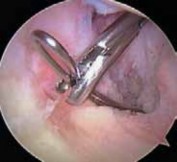

TECHNIQUES TECH FIG 1 • The posteromedial portal is established under direct visualization using a spinal needle. 1. Using an arthroscopic electrocautery device and shaver, overlying synovium and ruptured PCL fibers are débrided, and the superior interval between the ACL and PCL is defined.

2. An accessory posteromedial portal is created just proximal to the joint line and posterior to the MCL.

1. A 70-degree arthroscope is placed between the PCL remnants and the medial femoral condyle to assess the posterior horn of the medial meniscus and to localize the posteromedial portal with a spinal needle (

TECH FIG 1

).

2. A switching stick can be placed into the posteromedial portal to facilitate exchange of the arthroscope. The 30-degree arthroscope is used when viewing via the posteromedial portal.